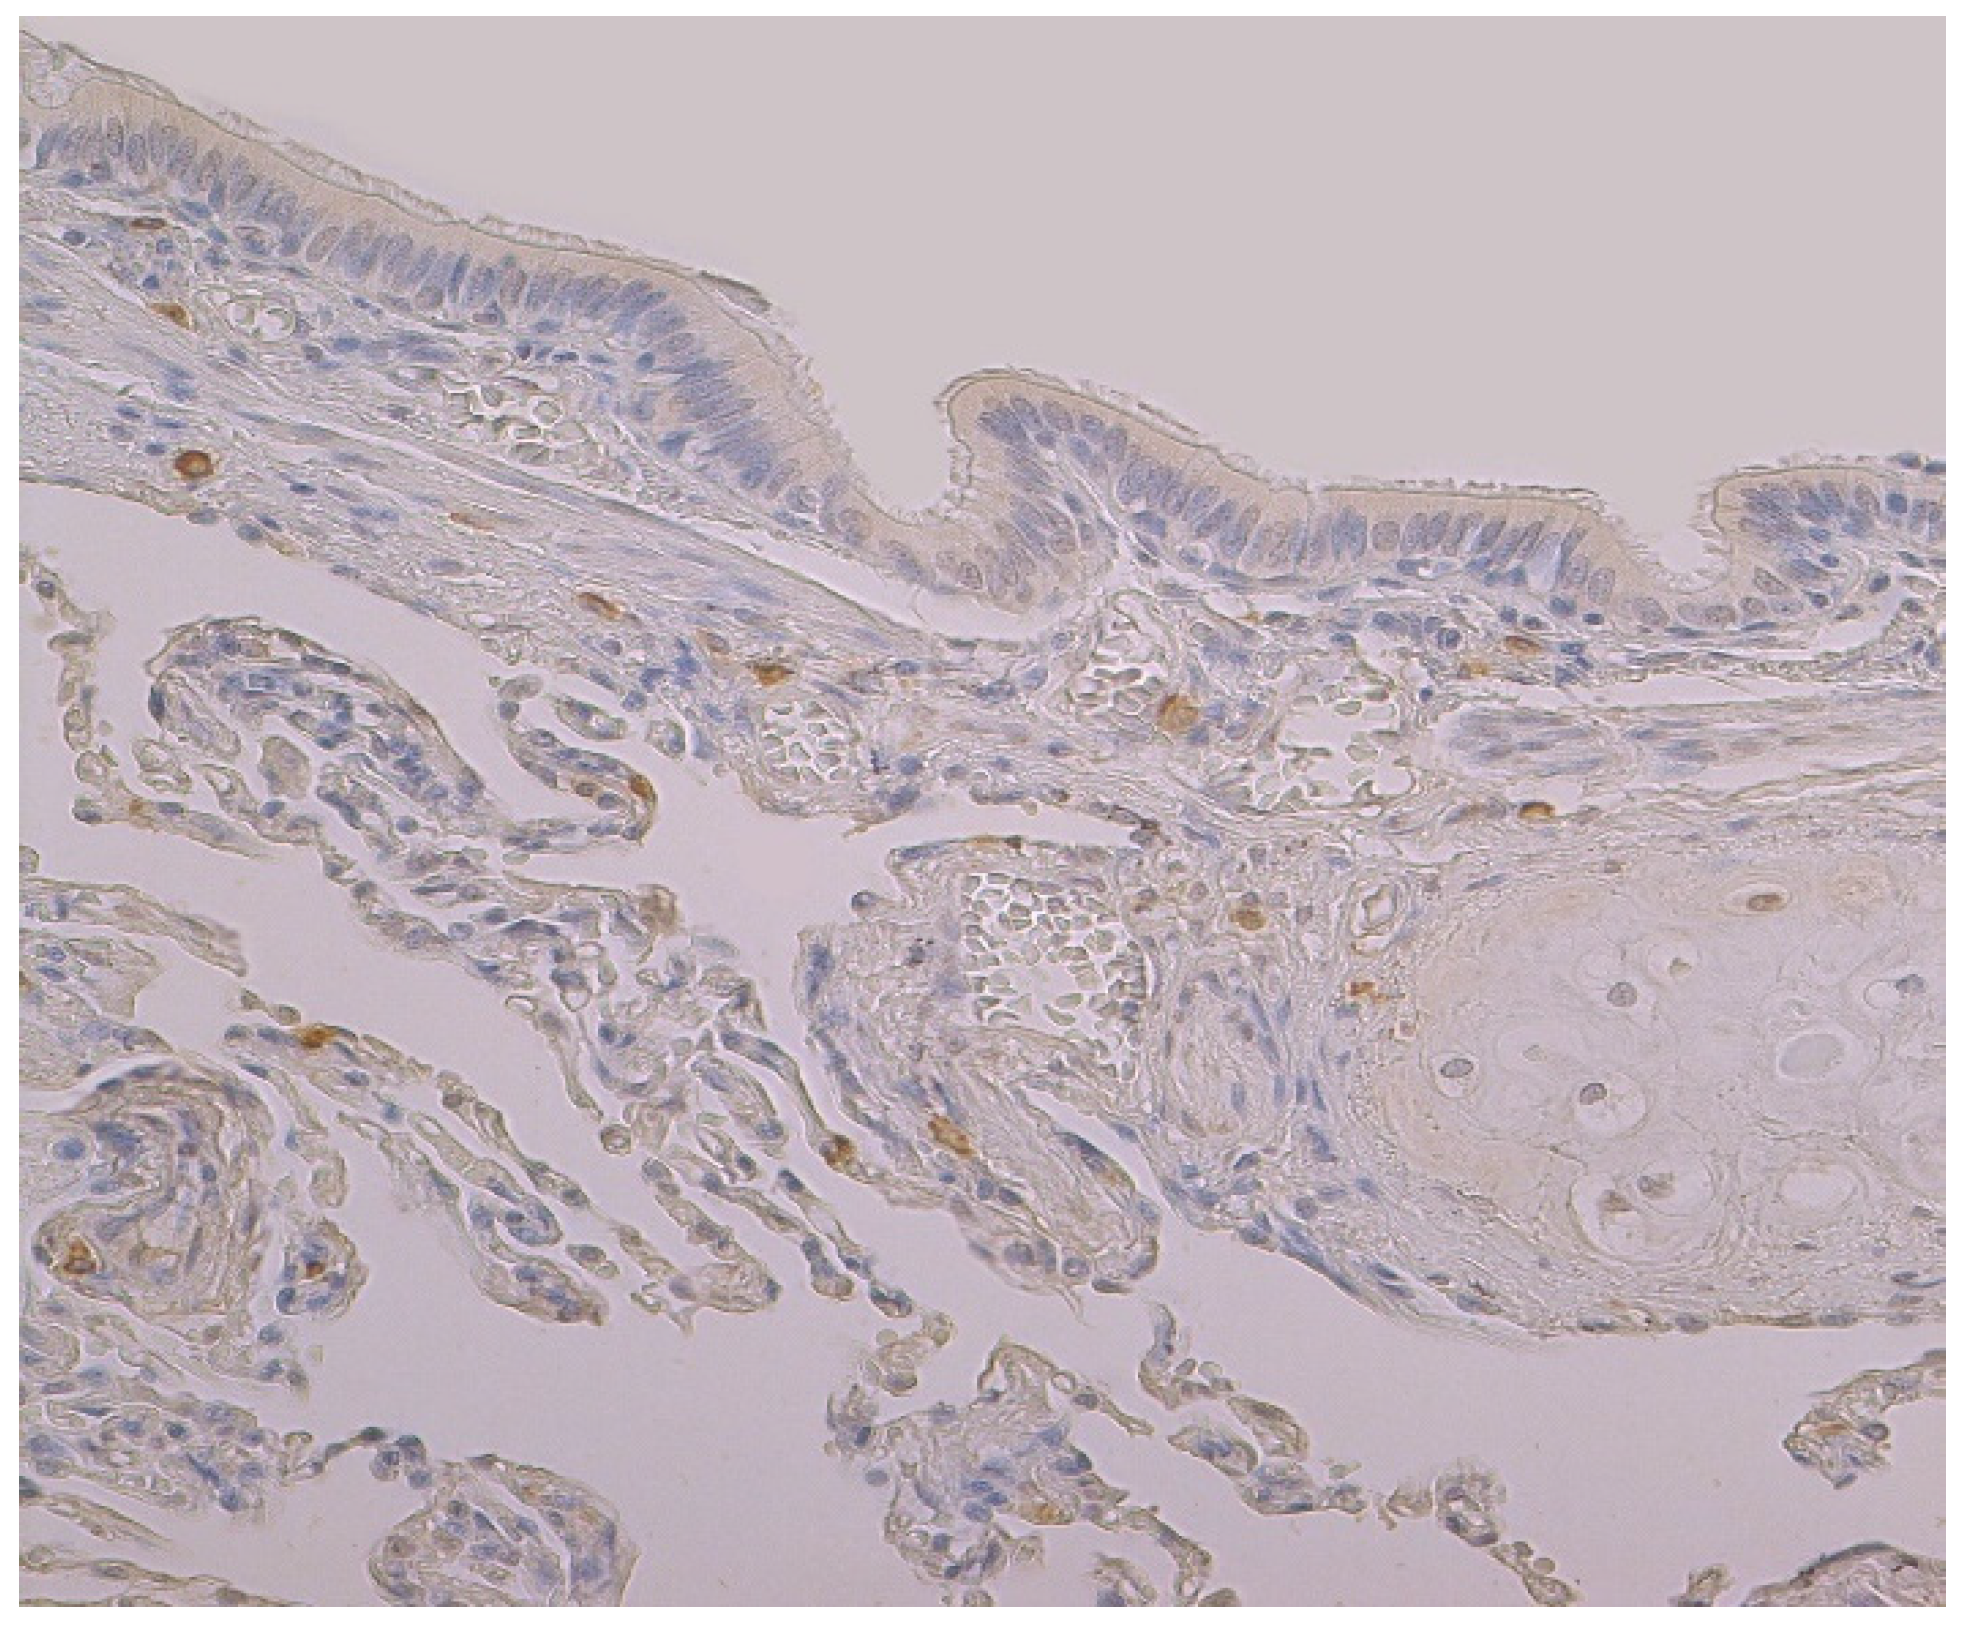

3.2. Immunohistochemical (IMH) Data